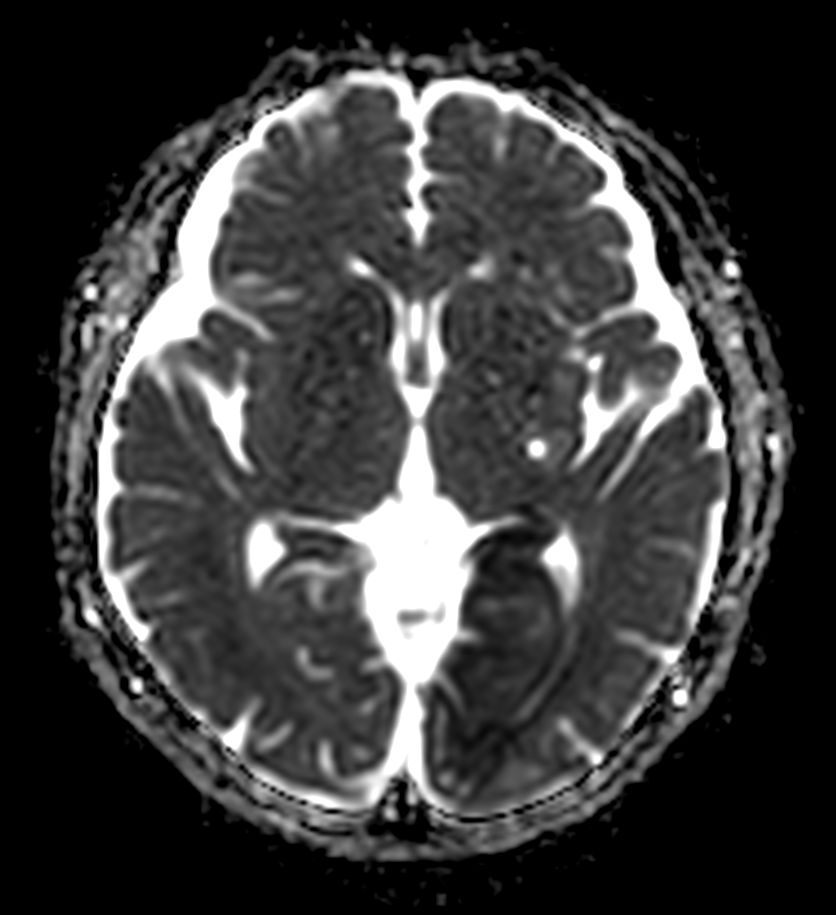

Brain infarction

Patient with a brain infarction. Compressed SENSE is used to shorten the total exam time.

Diffusion - b1000

-